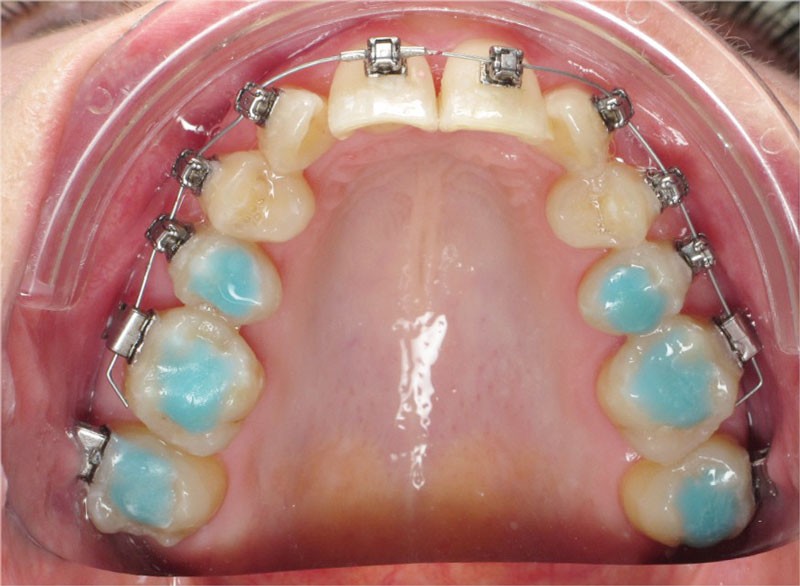

Un appareillage Damon métal a été mis en place, réalisé à partir d’un set up numérique Insignia pour obtenir un contrôle précis des torques et de la forme d’arcade et réduire le temps de finition grâce à un collage indirect très précis.

De larges surélévations postérieures étalées ont été mises en place et la patiente a porté des élastiques précoces suivant les principes de la technique Damon. Les 14 et 24 rempliront le rôle des 13 et 23.

L’objectif, en utilisant la technique Insignia est de réduire le temps de traitement de 28 à 18 mois avec 12 rendez-vous (fig. 5 à 14).